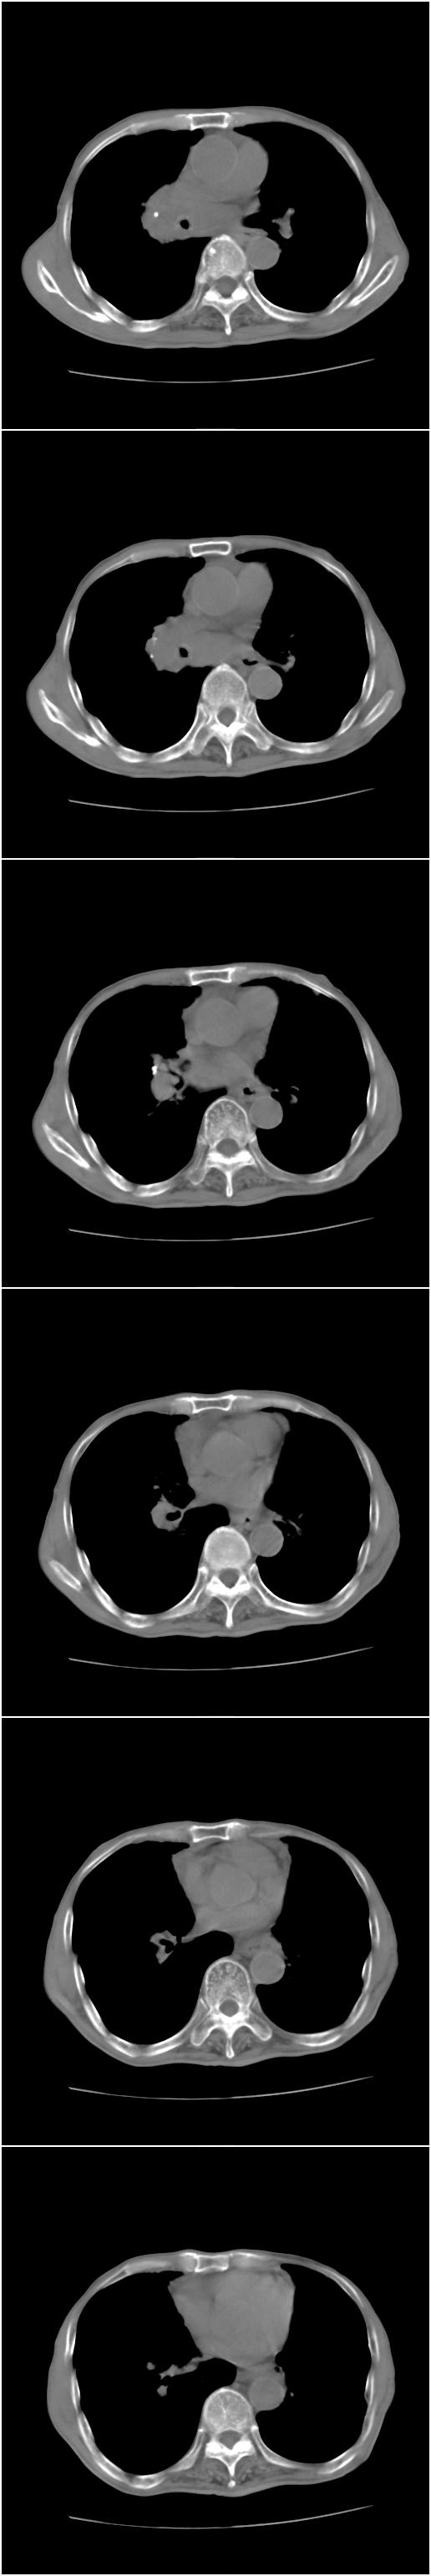

1、右侧中心型肺癌,右肺门,纵隔淋巴结转移可能性大。

2、贲门癌术后所见。

1)考虑为:右侧中心型肺癌并右肺门及纵隔淋巴结转移。2)贲门癌术后改变。